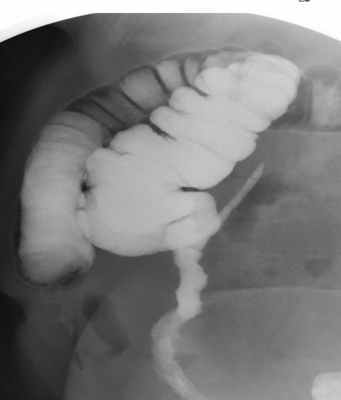

- ирригоскопия (рентген-исследование толстой кишки);

- ультрасонография; (эндоскопическое обследование толстого кишечника); (рентгенологическое исследование свищевых ходов с применением контрастного вещества); (инструментальное исследование прямой и сигмовидной кишки);

- Ирригоскопия (по показаниям);

- рентген с применением контраста (ирригоскопия, фистулография) — для выявления ответвлений и затеков сложных свищей;